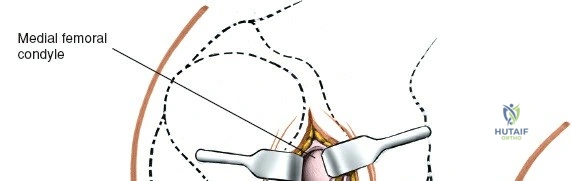

Gross Anatomy of the Medial Meniscus

The medial meniscus is a C-shaped, semilunar fibrocartilaginous structure that resides on the medial tibial plateau, acting as an interface between the femoral condyle and the tibial plateau. It is broader posteriorly than anteriorly.

- Posterior Horn: The broadest part, attaching firmly to the posterior intercondylar area of the tibia, anterior to the posterior cruciate ligament (PCL) insertion. It also has a strong attachment to the semimembranosus muscle tendon, which exerts a posterior pull on the meniscus during knee flexion, potentially influencing its stability and tear patterns.

- Landmarks: Palpate the medial joint line, medial epicondyle of the femur, and medial tibial plateau. The saphenous vein and nerve courses superficial and posterior to the medial femoral condyle, requiring careful attention.

Exposure of the Meniscus:

- Retractors are carefully placed to expose the medial tibiofemoral compartment. Self-retaining retractors may be used, but care must be taken to protect the articular cartilage.

- To improve visualization, the knee is brought into hyperflexion (as per seed content, "beyond a right angle"). This maneuver, combined with external rotation of the tibia and a valgus stress applied to the knee, widens the medial compartment. This allows for improved access to the posterior horn of the medial meniscus.

Meniscectomy Technique (Partial):

- Inspection: Thoroughly inspect the medial meniscus to identify the tear pattern and assess its stability using a blunt probe.